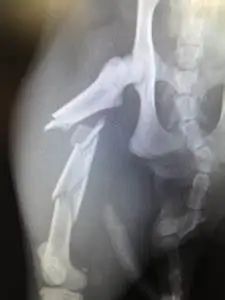

如果猫咪走路一跛一跛的,或者谋职教抬起来走路、甚至出现明显变形和骨头直接外露,表示猫咪有可能骨折了!!